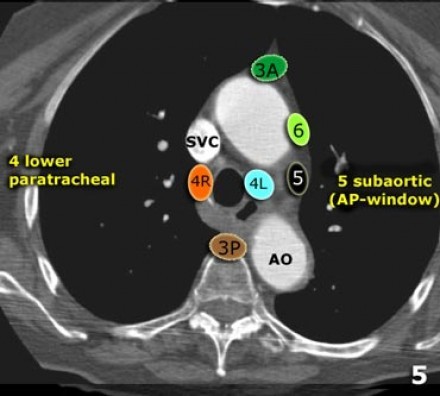

5. Linfonodos Subaórticos

4R. Paratraqueais Inferiores Direitos

Limite superior: intersecção da margem caudal da veia inominada (brachiocefálica esquerda) com a traqueia.

Limite inferior: borda inferior da veia ázigo.

Linfonodos 4R estendem-se para a borda lateral esquerda da traqueia.